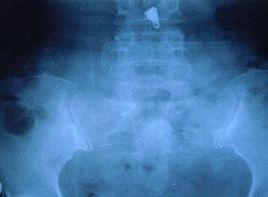

3.X線平片:同時拍攝正位及側位X線片,疑及骶髂關節受累者,應加拍斜位片。除觀察骨折線外,還需以此進行分型及決定治療。因該處腸內容物較多,拍片前應常規清潔灌腸。